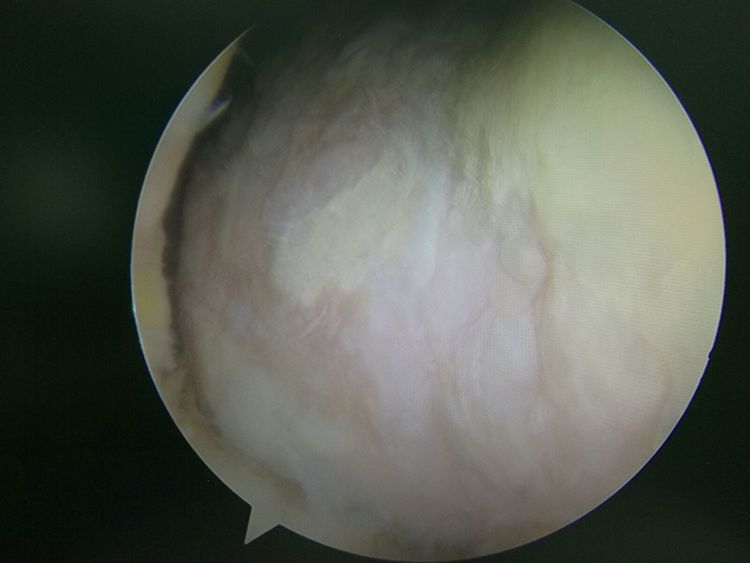

镜下手术图片,展示人体关节镜下情况:

骨科中心近两年共收治关节镜手术病人500余人,本人在近半年共收治关节疾病患者70余人,包括肩关节脱位及盂唇损伤、半月板损伤、交叉韧带损伤、叉韧带止点撕脱、髌骨脱位、色素性滑膜炎、关节游离体、老年骨性关节炎、踝关节外侧副韧带损伤伴距骨软骨损伤等。均通过关节镜或辅助关节镜手术治疗,短期内随访效果好,总体满意率在95%以上。